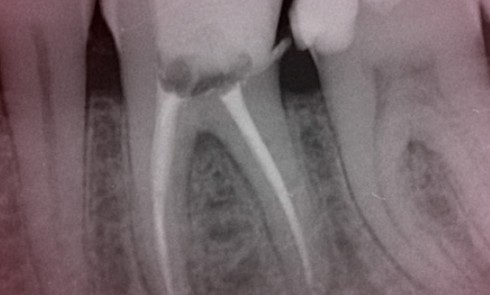

Article réservé à nos abonnés L’obturation canalaire avec une nouvelle famille de biomatériaux… en toute simplicité (partie 1)

Les objectifs du traitement endodontique sont souvent restreints à des notions mécaniques. Pourtant, l’objectif principal reste de prévenir toute agression...